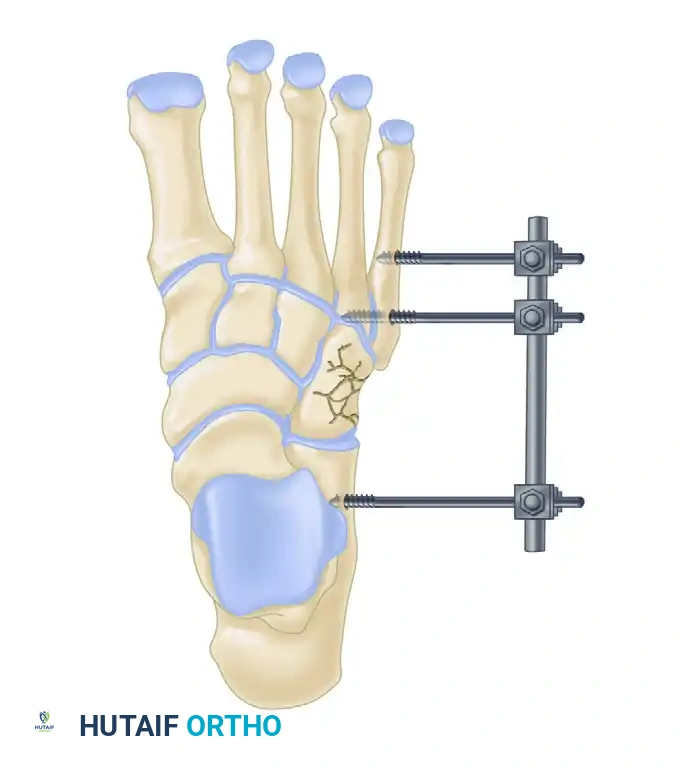

For severe displacement resulting in shortening of the lateral column, ORIF is mandatory. Restoring lateral column length is critical to prevent a severe abduction deformity of the foot. External fixation or a femoral distractor may be necessary to pull the lateral column out to length before structural bone grafting and plate fixation can be applied.

Cuneiform Fractures

Isolated cuneiform fractures are exceedingly rare. Nonoperative treatment is reserved for strictly nondisplaced fractures. Displaced fractures require ORIF. If the cuneiform is highly comminuted, temporary bridge plating or external fixation is required to maintain the length and alignment of the medial column.